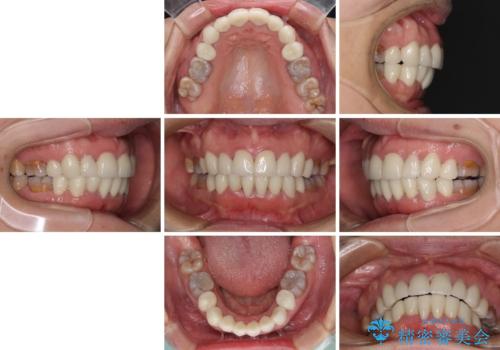

- 小さいころからの歯の変色と矯正治療の後戻りを気にして来院された患者様です。

気になる変色歯を仮歯に変え、その後歯列不正を矯正治療で改善し、最後にオールセラミッククラウンにて補綴治療することとしました。

数十年に及んだ歯の変色が改善されたため、大変満足していただきました。